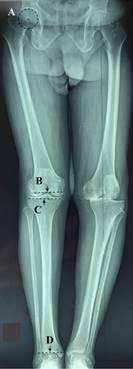

To achieve this post-surgical alignment it is necessary to remember all of the measurements to be included in preoperative planning.2,3,4,5,6,7,8,9,10,11 Initially, we must identify the center of the femoral head, the joint center of the distal femur (JCDF),12,13 the joint center of the proximal tibia, and the joint center of the ankle (Figure 1);14 which will allow us to draw the following axes: femoral anatomical axis (FAA), tibial anatomical axis, femoral mechanical axis (FMA), tibial mechanical axis, distal femoral osteotomy (DFO) line and tibial joint line (Figure 2). The line to connect the center of the femoral head to the joint center of the ankle is named the load axis, mechanical axis, or Maquet line.15,16,17

Figure 1:The preoperative planning begin to identify: A) center of femoral head, B) joint center of distal femur (midpoint of the femoral length at the height of the notch without considering osteophytes), C) joint center of proximal tibia (midpoint of the tibial length immediately distal to the articular surface without considering osteophytes), D) joint center of ankle (midpoint of tibiofibular length parallel and proximal to the line to connect the medial- lateral articular surfaces of talus).